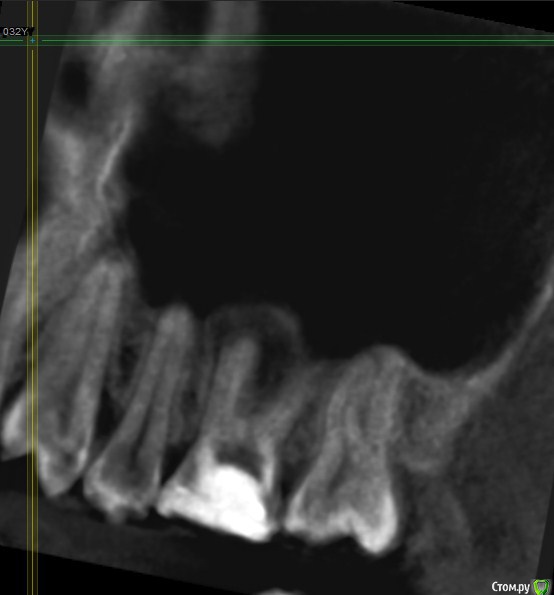

Подскажите, пожалуйста, точно удалять? Как принять это решение, все таки надежда на какой то другой лечебный вариант теплится =)post-59509-0-08196600-1578493080_thumb.jpgpost-59509-0-63211400-1578493088_thumb.jpgpost-59509-0-77705800-1578493096_thumb.jpgpost-59509-0-02698500-1578493106_thumb.jpgpost-59509-0-04880900-1578493120_thumb.jpgpost-59509-0-11411000-1578493128_thumb.jpg

По представленным срезам создаётся впечатление, что лечение вполне возможно